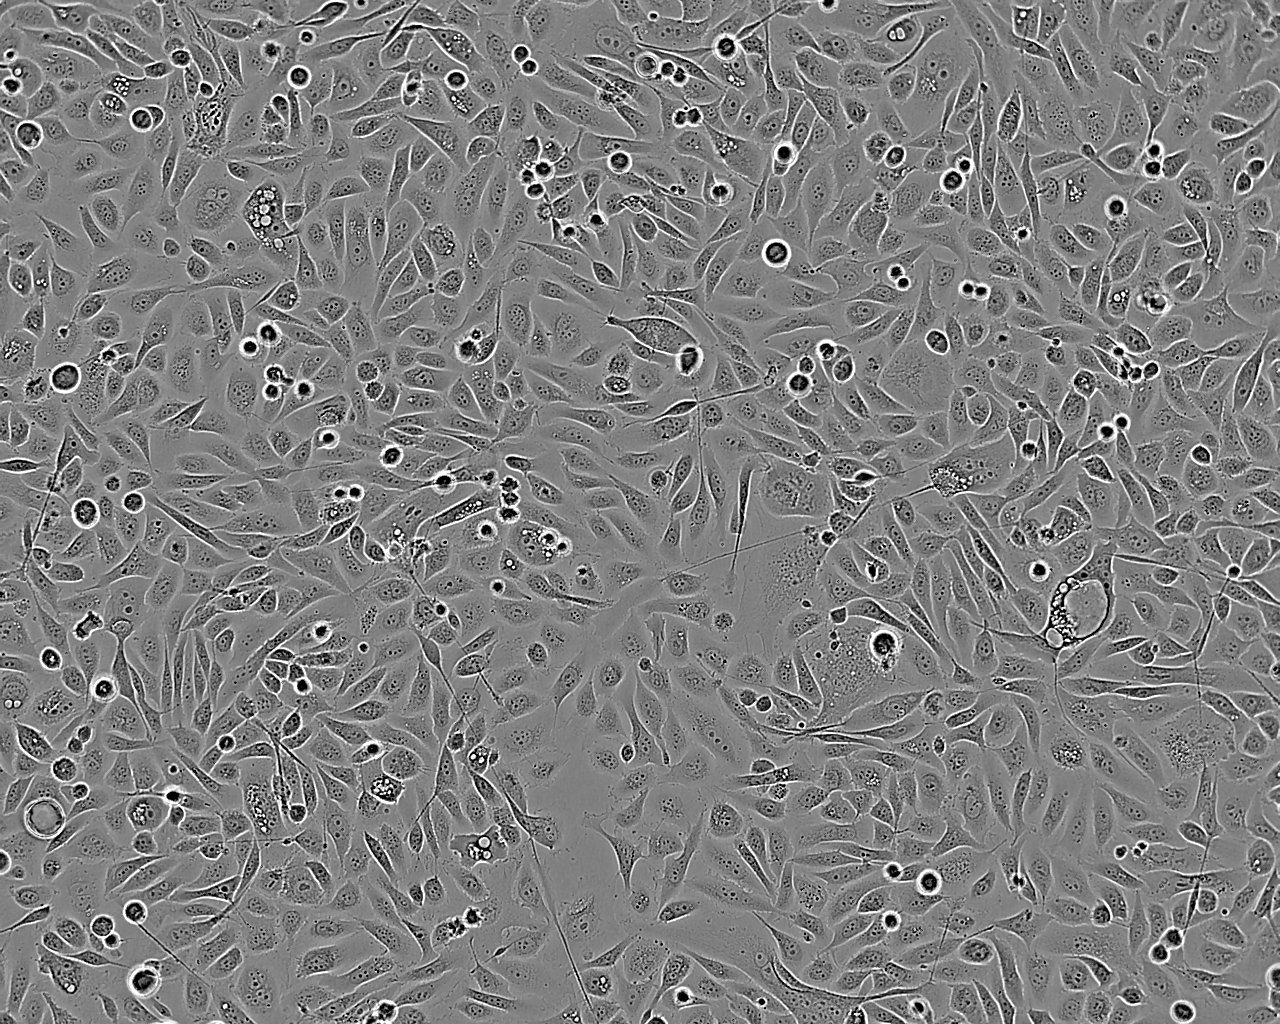

Images

Split sub-confluent cultures (70-80%) 1:2 to 1:6 i.e. seeding at 2-5x10,000 cells/cm² using 0.05% trypsin/EDTA; 5% CO₂; 37°C. Medium change every 5 days. The initial subculture interval after cells are thawed may be longer than 7-9 days.

Growth Mode